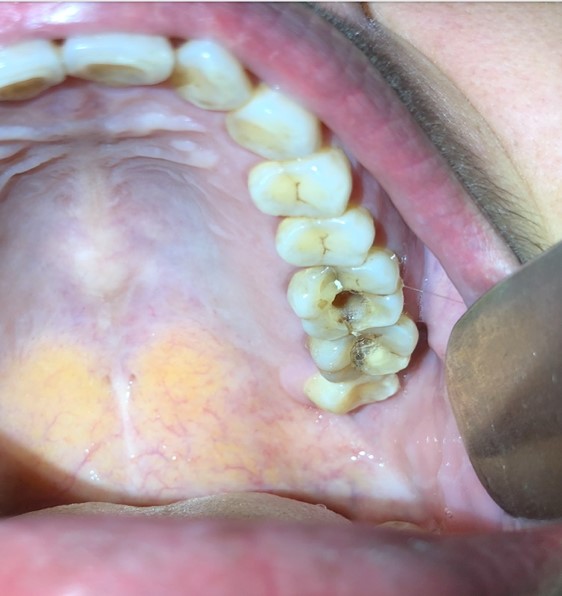

–         Chẩn đoán hình ảnh: hiện nay chủ yếu chỉ định phim chụp cắt lớp vi tính mũi xoang và chụp Conebeam CT, giúp đánh giá đồng thời đặc điểm bệnh lý của xoang hàm và răng liên quan, đồng thời là bản đồ để bác sĩ lập kế hoạch can thiệp hiệu quả.

viem xoang 21

Hình 2. Đường thông giữa ổ viêm chân răng với xoang hàm trên phim chụp Conebeam CT